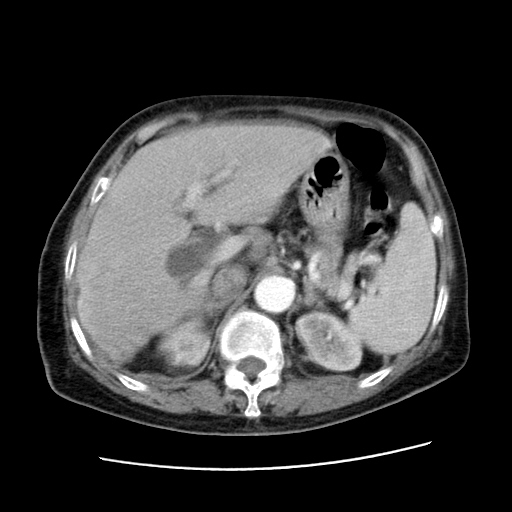

女,77.无不适

肝脏变异、异位胆囊,肝右叶肝内胆管结石并肝内胆管扩张。

肝内胆管扩张,胆囊炎,胆囊窝积液。 右侧胸腔少量积液。

肝右叶肝内胆管结石并肝内胆管扩张。

肝右叶肝内胆管结石并肝内胆管扩张。胆总管下段梗阻,考虑壶腹部占位。

右侧肝内胆管局限性扩张,其内密度不均匀,扩张的胆管壁增厚,考虑肝内胆管炎合并结石可能性大